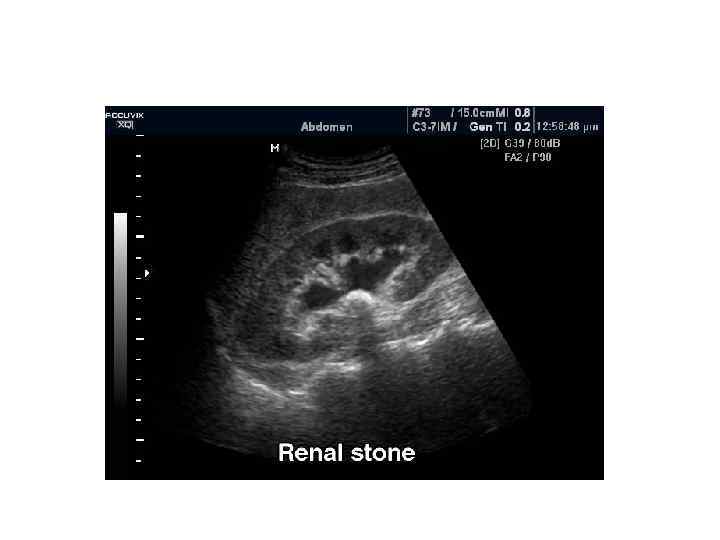

Методы диагностики • • • УЗИ Обзорный снимок брюшной полости Экскреторная урография Ретроградная урография Цистография Ангиография почечных сосудов КТ МРТ Радиоизотопное исследование почек

Показания к проведению УЗИ у детей: – Скрининг в возрасте 1 -2 мес – В случае антенатальной диагнстики аномалий почек сразу после выписки из роддома, если тяжесть состояния младенца не требует оказания помощи в первые сутки жизни – Скрининг каждые 2 года, в том числе обязательное обследование перед поступлением в детское учереждение, спортивную секцию – Неясная гипертермия без катаральных проявлений – Дизурические нарушения – Изменения в анализах мочи – Боли в пояснице или животе – Травма живота или поясничной области

УЗ размеры почек у детей • • Длинна 45 – 50 мм у новорожденного 62 мм к 1 -му году жизни Далее увеличение на 3 мм в год